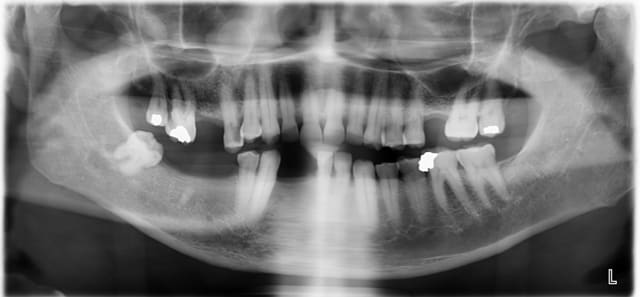

Voici le cas, patient d'une cinquantaine d'année se présentant pour solution prothétique.

Il a déjà un stellite mandibulaire de 10 ans, mais les édentements au maxillaire sup n'ont jamais été compensé.

Resultat: egression +++ de la 27 et 25

En bouche, on dirait sérieusement des dents de cheval, c'est impressionnant.

17: racines divergentes, aucune mobilité. Asymptomatique. Pulpe rétractée. Perte de substance importante. Fortement égressée. Le patient n'a pas de parodontite, il a perdu 1 mm d'os en 50 ans. Dent indestructible, elle continuera à égresser jusqu'à toucher la muqueuse en bas et restera immobile tant qu'il restera un peu d'os autour des apex.

Tu dis que tu vois la furcation en vestibulaire mais sur la radio la furcation est encore fermée par de l'os.

Il y a un projet prothétique en antagoniste: sur 17 tenant compte de ces éléments on fait endo, IC, CR.

15 idem + énorme carie juxtapulpaire à moins que ce ne soit la lacune d'usure en vestibulaire. En tous cas délabrée, égressée MAIS immobile et asymptomatique, le rapport CR clinique/racine n'est pas si mauvais, tu dis 1/2 à 1/2 il parait plutôt 2/3 à 1/3 et quand tu auras remis la dent dans le plan occlusal ce sera 3/4 à 1/4.

D'où: endo, IC, CR.